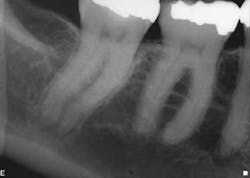

However, when the anatomy is the most complicated with multiple curves or the smallest canals, a different file system might be a better choice (Figs. 3 and 4). Although almost all root canals can be treated with WaveOne, in certain anatomies the root canal procedure is actually easier and more efficient when utilizing a file system that has more tip sizes and taper choices and ultimately requires more files. Vortex Blue (Dentsply Tulsa Dental Specialties), with its incredible resistance to cyclic fatigue and reduced shape memory, is an ideal file choice in this clinical situation. Vortex Blue files have tip sizes ranging from ISO 15-50 and tapers of 0.04 and 0.06. This results in great flexibility to treat the most complicated canal anatomies — flexibility not only in the file itself, but also in the size and taper choices that are available. However, to appreciate the metallurgical advantages of the Vortex Blue files, it may be necessary to spin four or as many as six files per canal.

Fig. 3: Preoperative anatomy of tooth No. 31 shows a double curve in the mesial root canal. The size, length and taper of the root suggest a file system with multiple tip and taper choices would be most suitable.

Fig. 4: A glide path was established with a 15/0.04 Vortex Blue rotary file in conjunction with size 10 hand files. Vortex Blue files were then used in sequence until a final shape of 30/0.04 was achieved in the mesial root and 30/0.06 in the distal root.